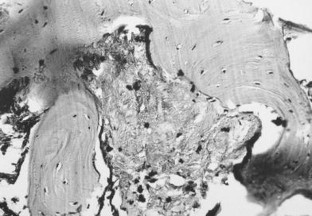

Fig. 2